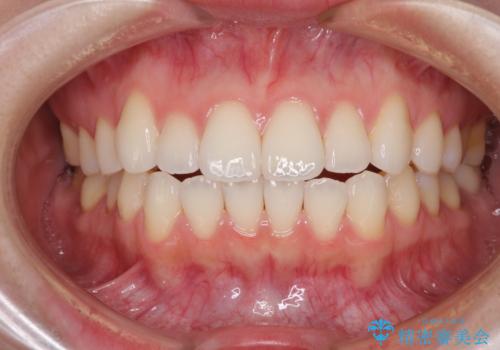

- 矯正治療の後戻りを気にして来院された患者様です。

後戻りは軽微でしたが、舌突出癖が認められ、初診時には上下前歯に舌がはまるスペースができていました。

舌突出癖の改善を行いながら、インビザライン・ライトにより矯正治療を行うこととしました。

舌突出癖の改善により上下前歯が接触するようになり、前歯でものを咬みきる必要のある食事がスムーズに行えるようになりました。